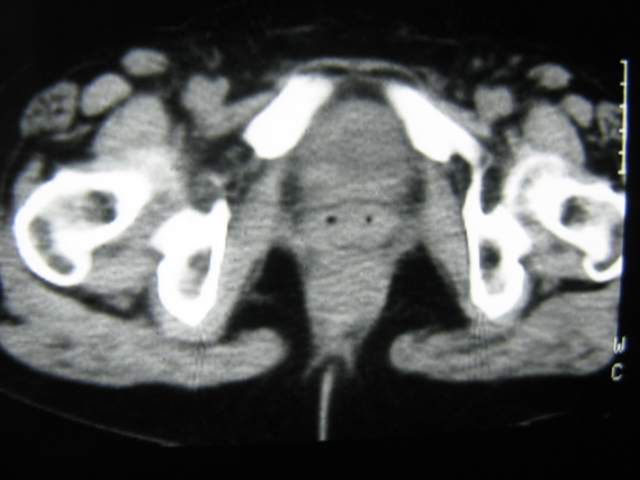

患者,女,64岁,2002年诊断为宫颈癌,当时只做过放,化疗。现在诊断:(1)宫颈癌。(2)直肠癌。请同道们讨论,探讨。另外肠壁为啥密度这么高,ct值约112hu。患者没有做过增强和造影。

高密度的不是肠管影,是肠管内的粪便影

患者直肠病变,排便不畅,粪便硬结造成,更高密度如钡灌肠者都可出现

硬结粪便能有如此高密度影?

我也碰到过几例,最离奇的一例是全结肠呈造影样高密度,患者直肠癌(首次发现),以往没有吃药,只有约半年时间长的胃纳差,排便不畅(据患者说每次大便只能拉出少许黄水)

不一定有意义,可清洁灌肠后复查